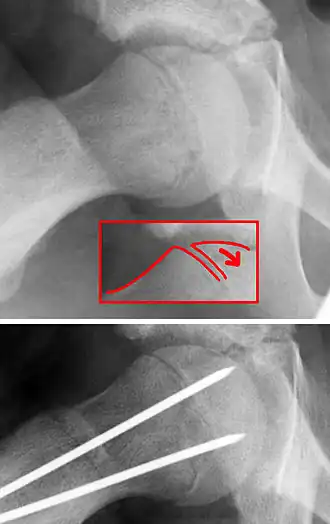

C'est le glissement en arrière et en bas de l'épiphyse proximale du fémur par rapport à la métaphyse. Ce glissement passe dans la zone hypertrophique du cartilage de conjugaison.

Sur le plan anatomique articulaire, les rapports de l'épiphyse et de sa surface articulaire (tête du fémur) avec l'acétabulum ne sont pas modifiés. Ce glissement est mieux compris en tant que glissement vers le haut et en avant de la métaphyse proximale du fémur (col) par rapport à l'épiphyse. Familiarisé avec cette manière de voir, le chirurgien visualise mieux les techniques opératoires.

- ostéosynthèse,